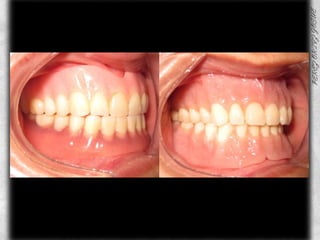

COMPARATIVOS

PROTESIS TERMINADA

AJUSTE OCLUSAL